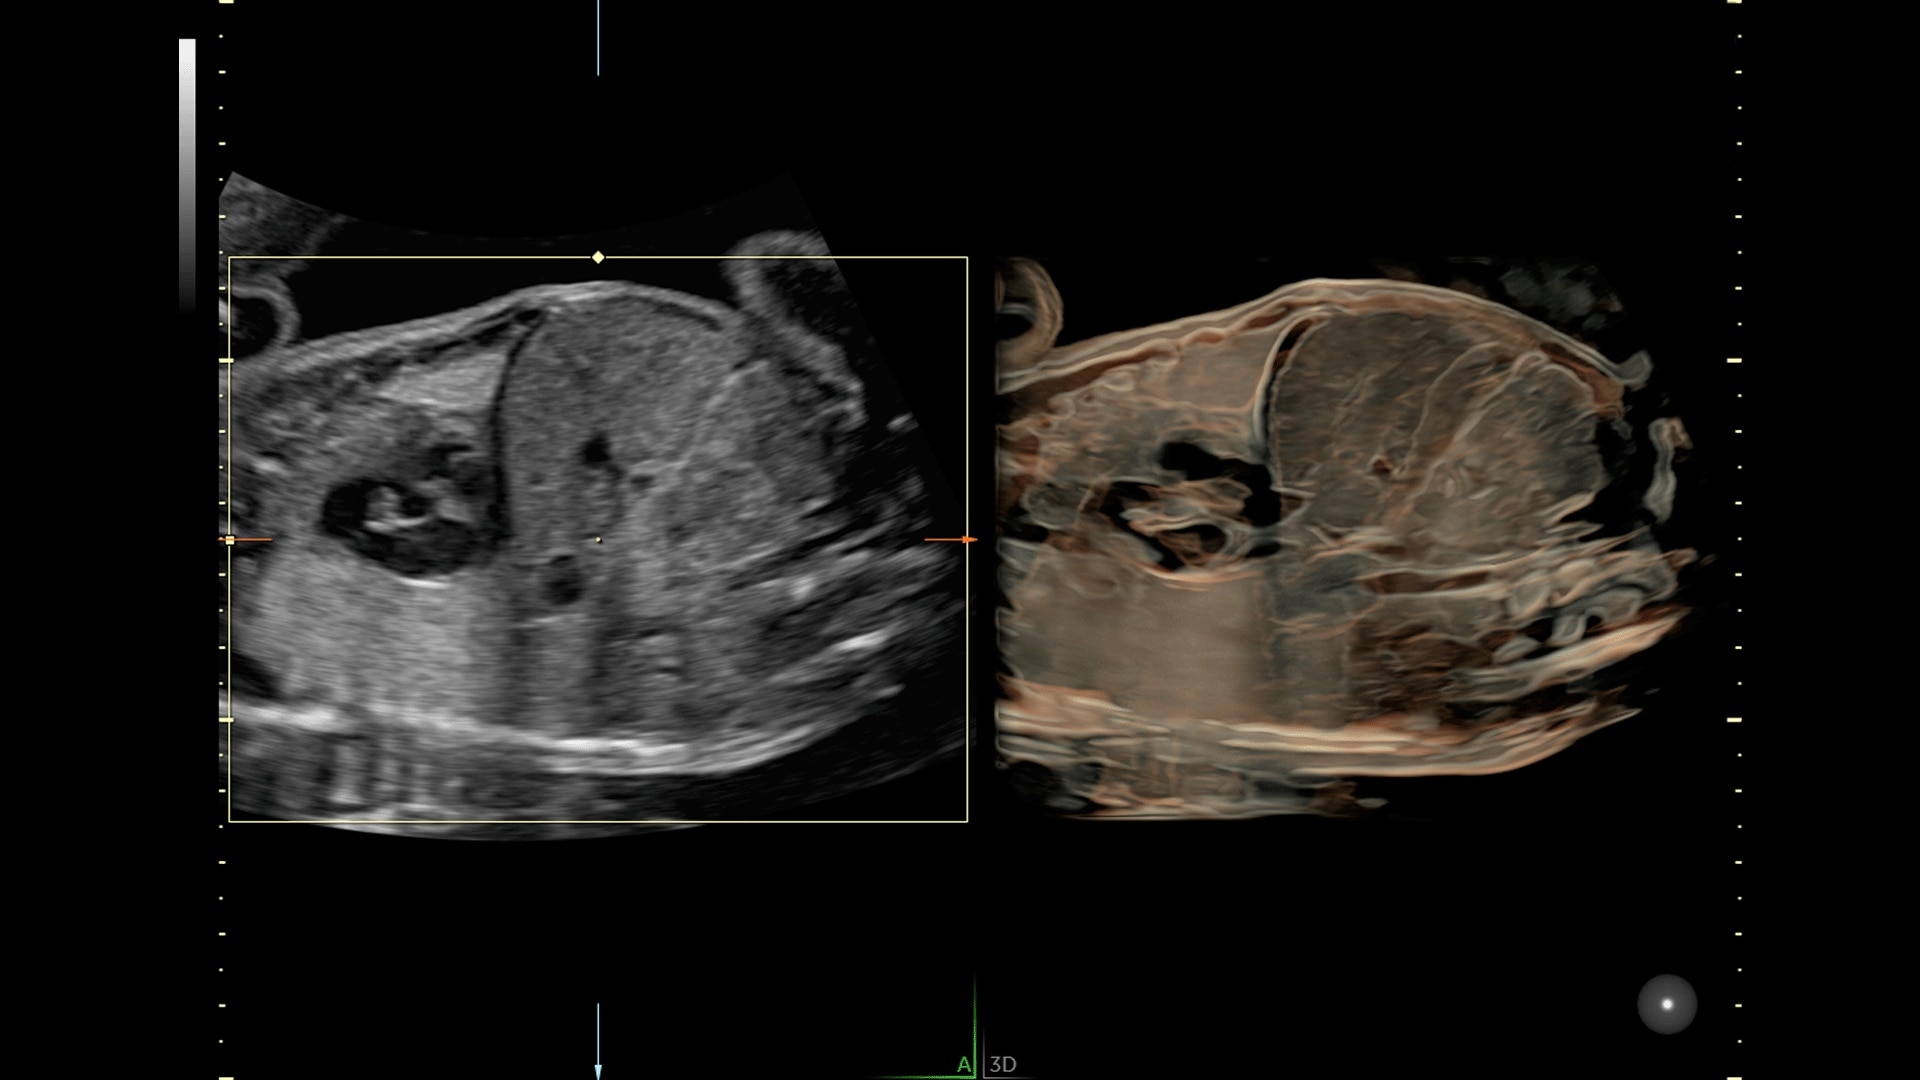

Generate spectacular 2D/3D and color Doppler images with increased penetration and stunning clarity, to help visualize critical details needed for diagnostic assurance. The Lyric Architecture unlocks new imaging and processing power to expand your imaging capabilities for years to come